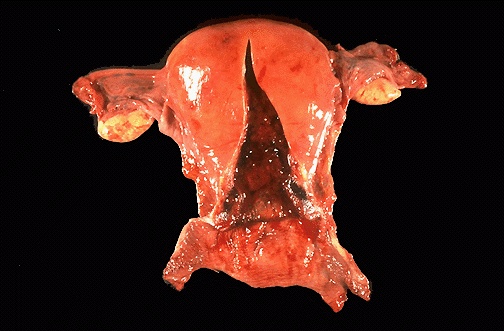

This is a normal postpartum uterus 5 days following delivery. Note how quickly the uterus is returning to its normal non-pregnant size.